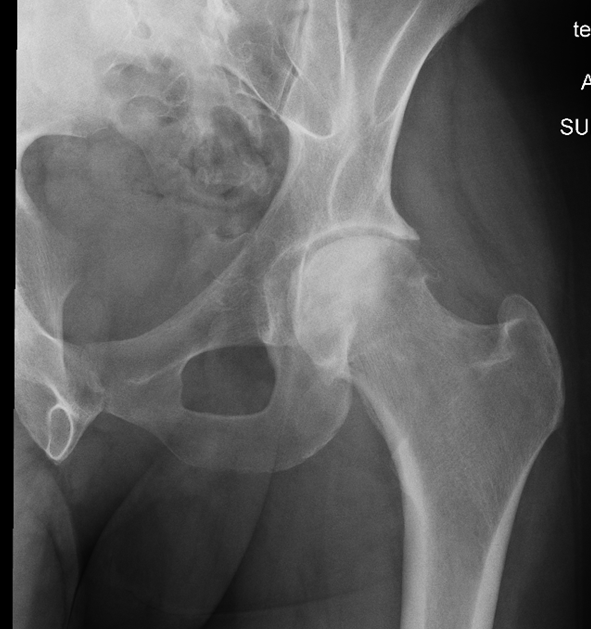

Pelvis/Hip Case 1

This HIV patient has bilateral hip pain worse on the left for 3 weeks. There's no history of trauma, and he's ambulatory with pain. What's the diagnosis and management?